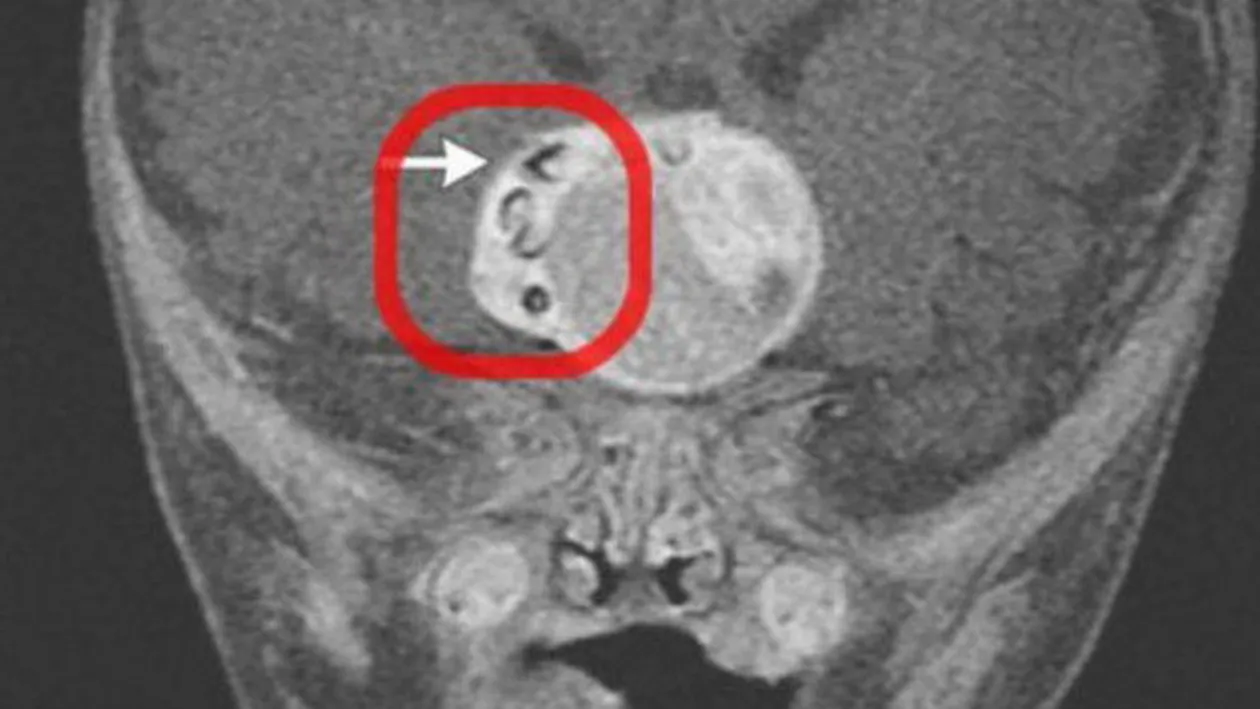

O echipa de doctori a facut o descoperire socanta. Au gasit un dinte care a crescut in creierul unui bebelus de doar 4 luni.

Forma rara de cancer a fost descoperita in creierul unui copilas din Maryland (SUA), anul trecut. Ciudata descoperire a fost publicata intr-o revista medicala.

Dintele crescuse intr-o tumora numita adamantinomatous craniopharyngioma.

Tumora avea 4.1 cm latime, 4 cm lungime si 3.5 cm inaltime.